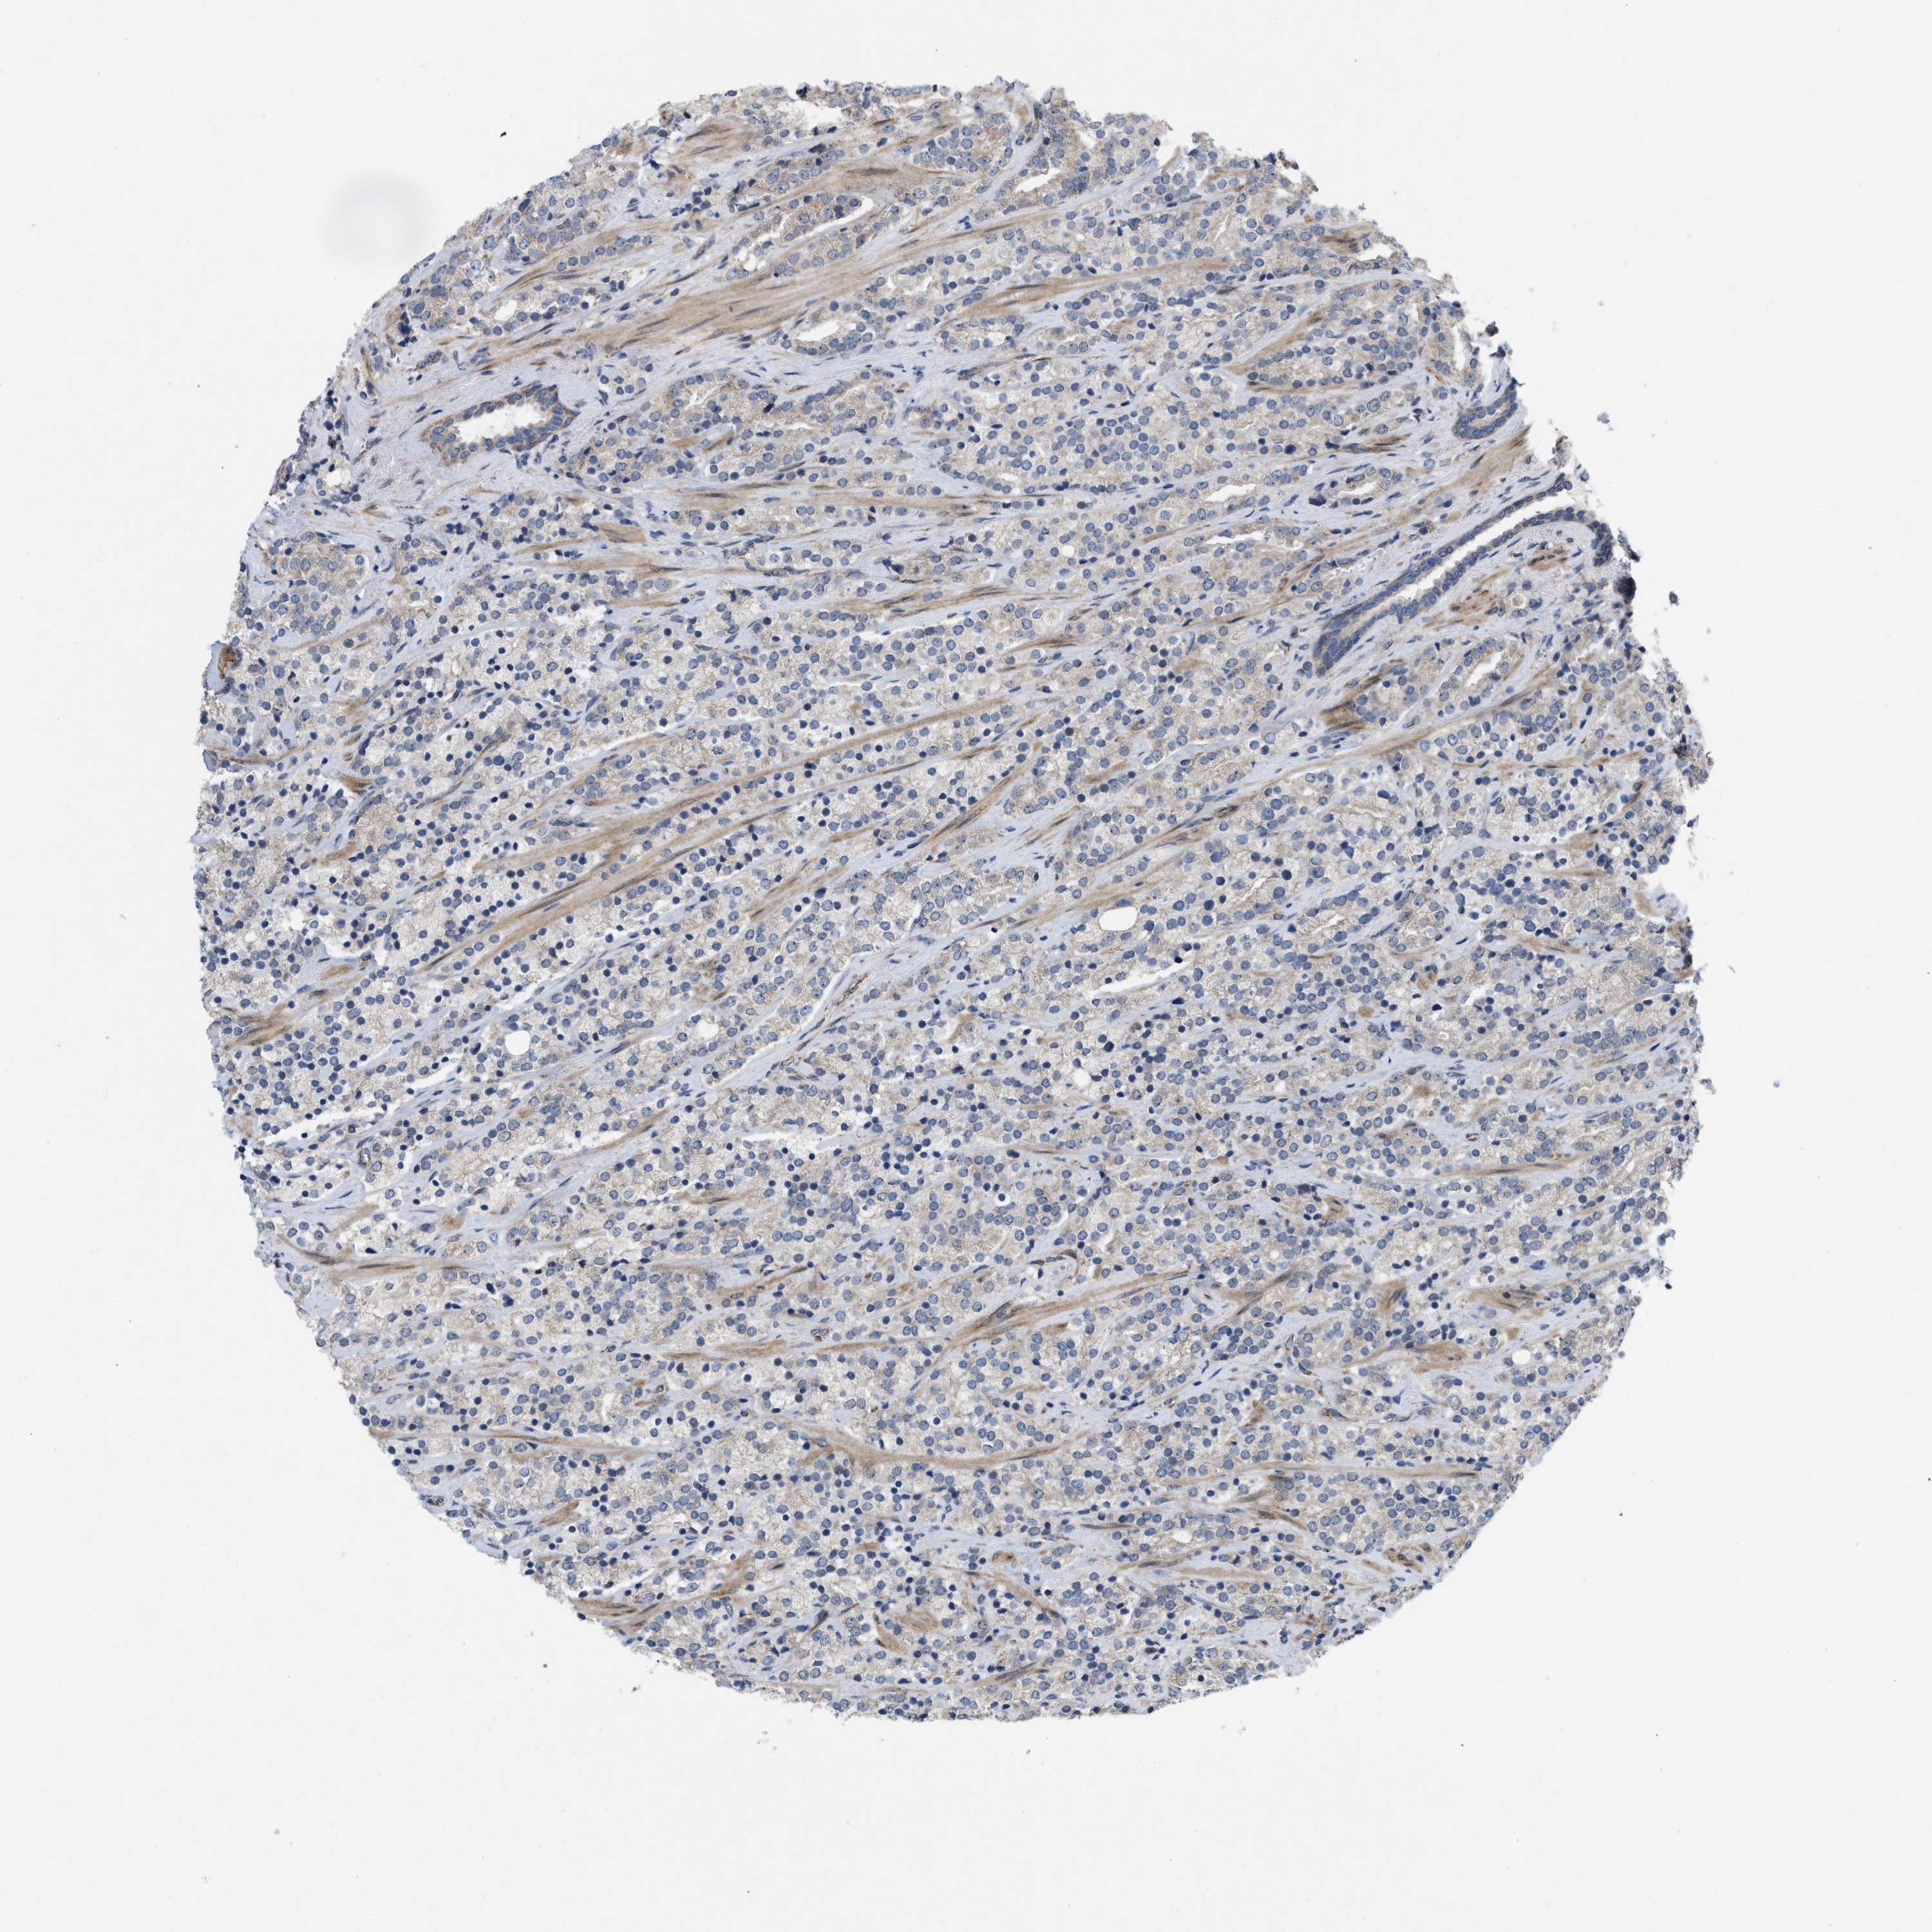

PROSTATE CANCER - Protein expressioni

A mouse-over function shows sample information and annotation data. Click on an image to view it in a full screen mode. Samples can be filtered based on level of antibody staining by selecting one or several of the following categories: high, medium, low and not detected. The assay and annotation is described here.

Note that samples used for immunohistochemistry by the Human Protein Atlas do not correspond to samples in the TCGA dataset.

Antibody stainingi

Antibody staining in the annotated cell types in the current human tissue is reported as not detected, low, medium, or high, based on conventional immunohistochemistry profiling in selected tissues. This score is based on the combination of the staining intensity and fraction of stained cells.

Each image is clickable and will lead to virtual microscopy that enables deeper exploration of all samples and also displays staining intensity scores, fraction scores and subcellular localization as well as patient and tissue information for each sample.

Antibody HPA019460

Staining

High

Medium

Low

Not detected

Intensity

Strong

Moderate

Weak

Negative

Quantity

>75%

75%-25%

<25%

None

Location

Nuclear

Cytoplasmic/membranous

Cytoplasmic/membranous,nuclear

Adenocarcinoma, High grade

Adenocarcinoma, Low grade